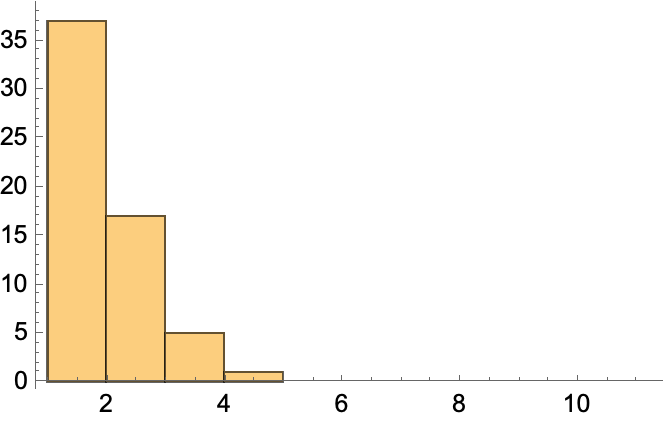

Change the style to highlight edges and vertices in the graph of a KEGG pathway:

| In[25]:= | ![ResourceFunction["KEGGPathway", ResourceVersion->"1.2.1", ResourceSystemBase -> "https://www.wolframcloud.com/obj/resourcesystem/api/1.0"][

Entity["TaxonomicSpecies", "MacacaFascicularis::3cnwm"], "p53 signaling pathway", "Graph", VertexSize -> {0.015, .008}, VertexLabelStyle -> Directive[FontFamily -> "Arial", 8], VertexStyle -> {"CASP8" -> Yellow, "CASP3" -> Yellow, Hue[0.31, 0.35, 1]}, EdgeStyle -> {"CASP8" \[DirectedEdge] "CASP3" -> Gray}]](https://www.wolframcloud.com/obj/resourcesystem/images/c26/c26fb78f-9391-4e5b-8348-1b3a9bcb8293/1-2-1/0155bd94f05c8297.png) |

| Out[25]= |  |